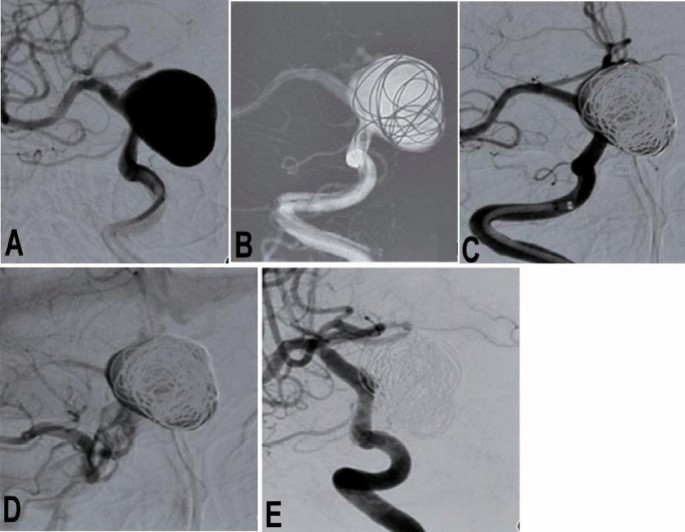

One hundred and forty-four PED Flex devices were all successfully deployed to treat 159 aneurysms harbored in the 131 patients, with the stenting success rate of 100% and a mean operation time of 123.7 ± 49.1 min (Table 2 and Figs. 1 and 2). A Flex device alone was used in 107 (67.3%) aneurysms while a Flex device combined with coiling was applied to treat 52 (32.7%) aneurysms. All devices had good coverage of the aneurysm neck with good wall adherence and patent parent artery. No patients experienced the “massage technique” or “balloon expansion” technique to make the PED device well adherent to the parent arterial wall. At discharge from the hospital, the mRS was 0 in 101 (77.1%) patients, 1 in 25 (19.1%), 2 in four (3.1%), and 4 in one (0.8%), with the good prognosis rate (mRS 0–2) of 99.2%.

A patient with a giant aneurysm at the right internal carotid artery ophthalmic segment was treated with a Pipeline embolization device combined with coil embolization. (A) Before endovascular procedure, the giant aneurysm was shown. (B) The aneurysm was firstly partially embolized with coils to promote thrombosis within the aneurysm sac and prevent possible aneurysm rupture before deployment of the Pipeline device. (C) After embolization, angiography revealed contrast filling inside the aneurysm sac. (D) In the venous phase, the contrast agent within the aneurysm was retained. (E) Follow-up angiography 4 months later showed complete occlusion of the aneurysm.